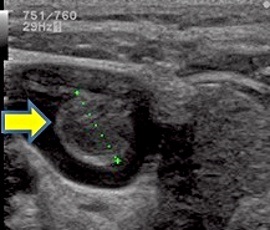

超音波画像(矢印:血栓)